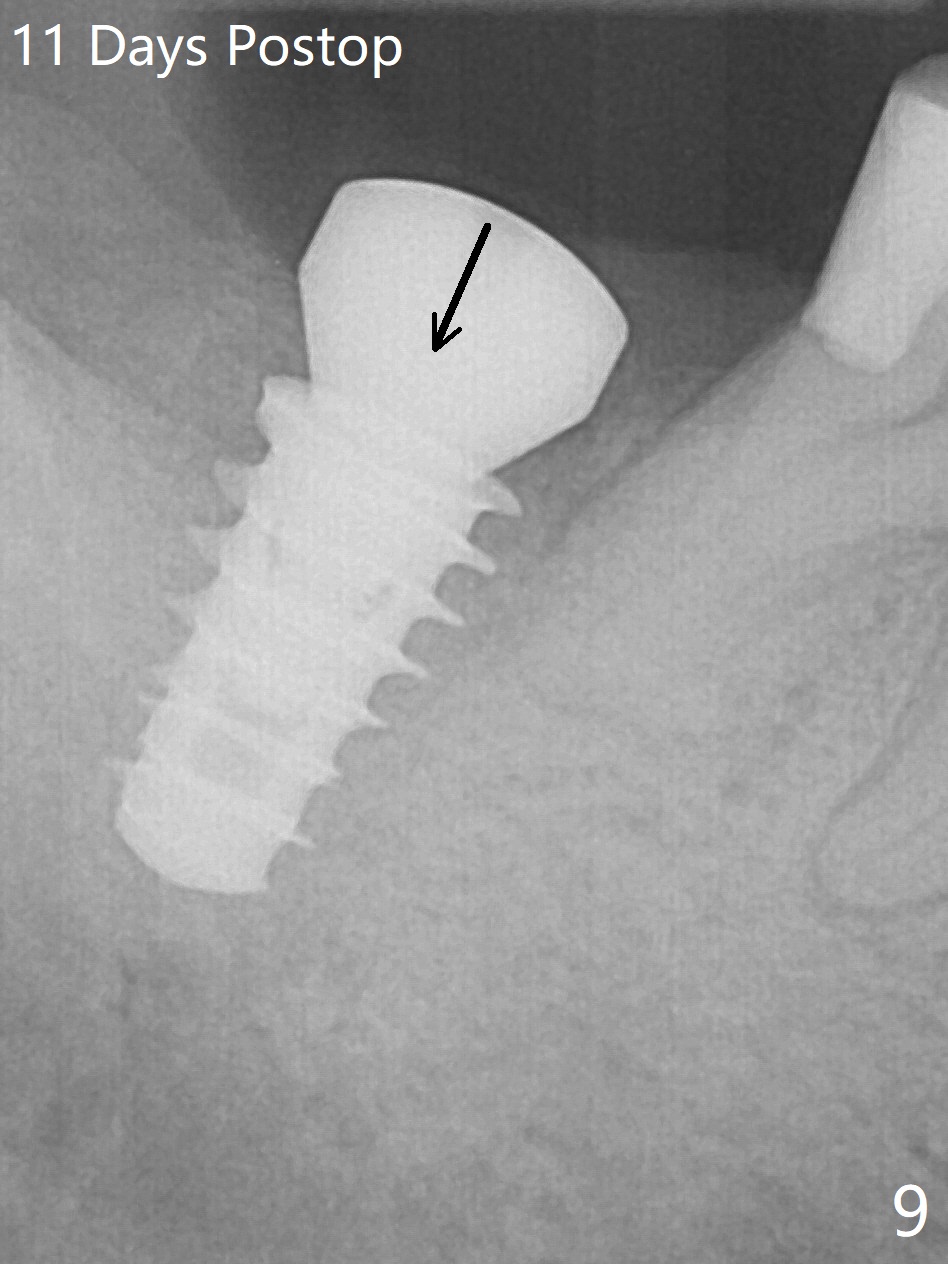

The socket shrinks with buccal plate reduction 3 months post socket preservation (Fig.5), as compared to 10 days postop (Fig.4). To restore the socket as much as possible, Magic Split is used (flapless), followed by Magic Expanders 3-3.8 mm for 11 mm (gingival level) and a 4x11mm dummy implant (Fig.6). The osteotomy is moved distal by using Lindamann bur; following 3.8 mm Magic Drill, a 4.5x11 mm dummy implant (Fig.7). Finally a definitive 5.5x9 mm implant is placed with <45 Ncm; a 6x2 mm healing abutment is placed to close the access (Fig.8). Autogenous bone harvested from the Magic Drill returns to the osteotomy mainly buccal prior to implant placement (Fig.8 *). The patient reports no discomfort immediately postop, thanks to the flapless technique. The patient has had postop pain; 11 days postop, the abutment and implant are found to be loose. After re-tightening by hand, the complex is seated deeper and more stable (Fig.9 arrow).